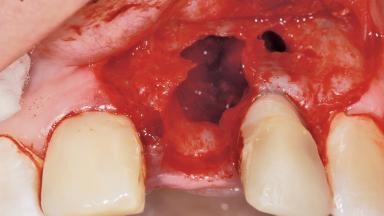

Late Placement of an Implant in a Maxillary Left Central Incisor Site

A 36-year-old female patient was referred for the replacement of the upper left central incisor (tooth 21), which had fractured. Although the tooth had been asymptomatic for many years, the crown began to loosen, at which time she presented to her dentist for an assessment. Teeth 21 and 22 had both been endodontically treated many years previously. She was a healthy individual and a non-smoker.

Bone Volume Deficient horizontally, requiring prior grafting